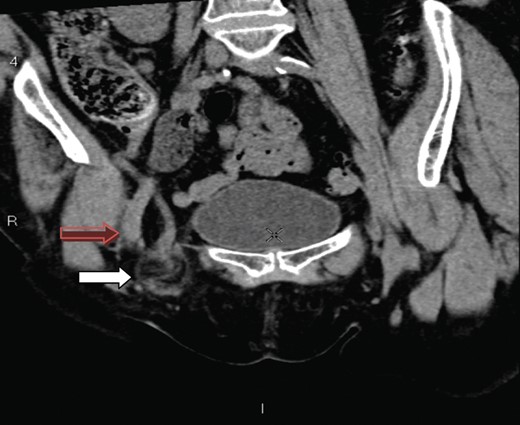

A 70-year-old female was referred by her general practitioner to our radiology department after presenting with a painless right groin swelling. An ultrasound scan showed a lymph node in the right groin with surrounding fluid and unusual appearances not typical of a hernia. A limited CT scan was subsequently performed which revealed a right femoral hernia containing the tip of the vermiform appendix with surrounding inflammatory change and an associated enlarged lymph node in keeping with a De Garengeot's hernia (Figs 1–3). On questioning, the patient first noticed the lump 2 weeks prior to presentation and said that it has gradually increased in size. It was not painful and she had no obstructive symptoms. Her medical history included COPD, breast cancer and a past history of tuberculosis.

A coronal section showing the tip of the appendix (white arrow) protruding through the femoral canal, medial to femoral vein (red arrow) into the hernia. The appendix measures 10 cm.